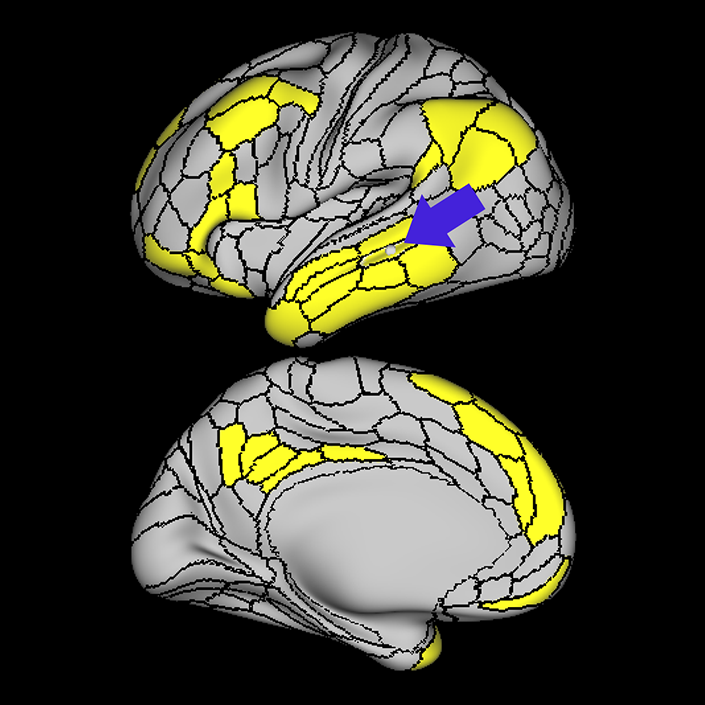

Language Network

Why we think this network is worth considering in decision making:

Disturbances of language have been linked to anatomic disruption of the human language network architecture for nearly 150 years.

Evidence that this network is responsible for useful function in humans:

While details regarding its exact organization are still in refinement, the basic details regarding the anatomy of the human language system have been non-controversial for many decades, and there is a long and robust history of using models of the language system in clinical decision-making spanning back a very long time.

Exploring the language organization in the brain began in the mid-19th century with Broca’s and Wernicke’s studies on patients with defined brain injuries and lesions in the mid-19th century.1,2 Further studies identified a neural tract, the arcuate fasciculus, for connecting Broca’s and Wernicke’s areas being one of the major components of language processing in humans.3 Later on, more studies confirmed and expanded these findings using additional techniques such as cortical intraoperative mapping,4 and subcortical mapping,5 and neuroimaging using DTI and fMRI. Using DTI, Rilling et al., (2008) found a noticeable temporal projection of arcuate fasciculus that is much smaller or absent in non-human primates.6 Further studies reported a strong left lateralization of arcuate fasciculus in humans.7

Additional invasive tests have been described to study impact on networks for clinical decision making. Historically injecting sodium amytal into one carotid artery (Wada Test) has been the gold standard for finding out the language lateralization in the brain.8 Studies found a very strong correlation between Wada test and language lateralization.9 More recently, similar findings have emerged using non-invasive neuro-imaging techniques. One study reported fMRI superiority over Wada test predicting postoperative language function in patients when fMRI and Wada test are not consistent with each other.10 Moreover, a recent guideline by the American Academy of Neurology suggested fMRI may be considered as a replacement of Wada test in epilepsy.11

Consequences of damage to this network:

Evidence that damaging this network causes neurological decline.

Several studies demonstrated aphasic impairment as a result of damage to this network in stroke patients, epilepsy patients, and tumor patients.12,13,14

Lately, speech network has been successfully mapped using rs-fMRI in an aphasic patient with left temporal tumor even in the absence of cognitive function. In the study, patient was scanned before and after a seizure that causes aphasia for several days.15 In aged patients it was found that higher functional connectivity in the left language areas associated with higher scores in behavioral tests, this finding suggests a role for functional preservation in these areas.16